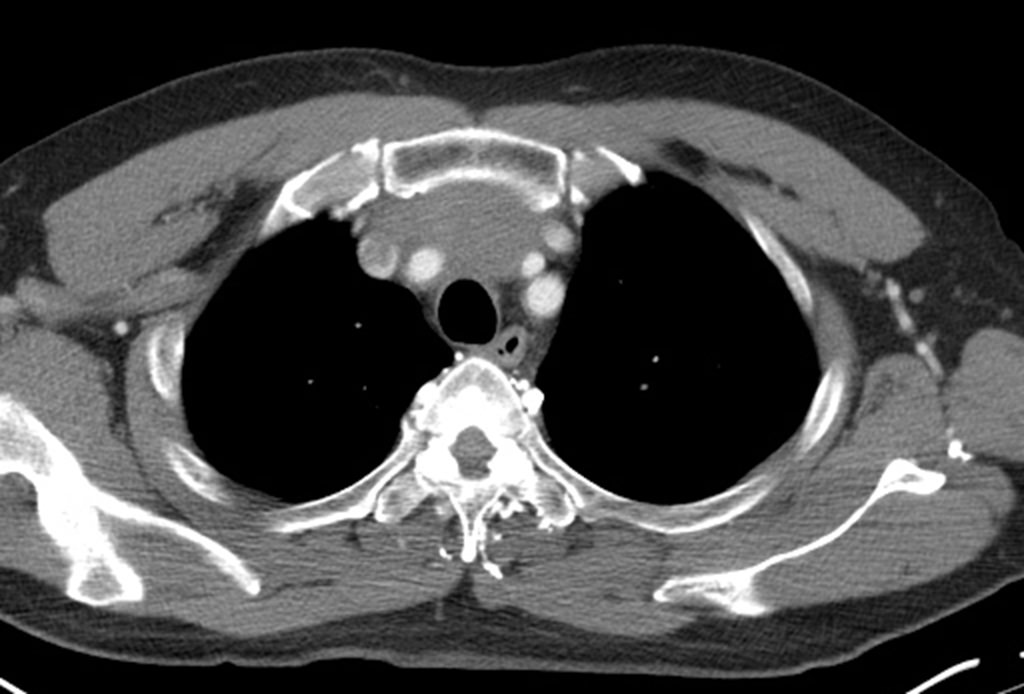

Anterior mediastinum tumor CT